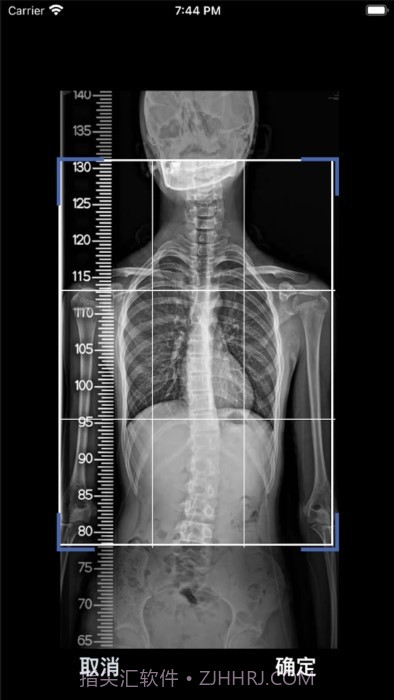

嗯,我感觉这款cobb角测量分析平台简直是医生和脊柱侧弯患者的福音!🌟 通过智能测量功能,能够迅速获取cobb角,准确率高得让人放心。对于有脊柱健康需求的小伙伴们来说,了解自己的状况特别重要,不仅能省时省力,更能随时存储和导出数据,后续分析也是轻松搞定!总之,这款应用为提高医疗效率、帮助患者掌握健康状况提供了强有力的支持,真心推荐给大家!

智能测量功能超赞,帮你快速获取cobb角,省时省力!

AI算法真牛,自动识别速度飞快,不用再手动调整。